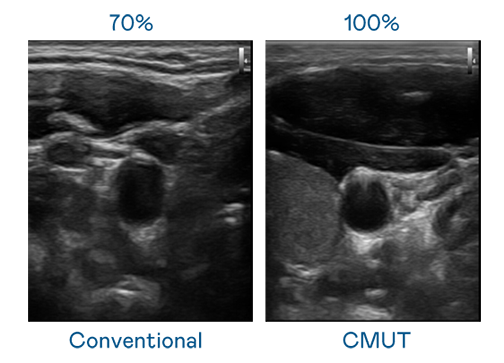

CMUT 技术是一种用电容式微机电元件来产生超音波讯号的技术。与传统 PZT 压电式技术相比,CMUT 频宽增加 30%,更宽频的超音波讯号让影像解析度大幅提升,是实现高影像品质医疗超音波扫描、促进精准医疗发展的关键技术。

大频宽带来超清晰影像

超音波影像的解析度高低,首先取决于探头能发出的讯号频宽。酷游 CMUT 可提供高清晰的超音波讯号,提供高频宽、高灵敏度、影像纹理细节更高的超音波影像,协助医护人员缩短影像判读时间及利用精准的医疗影像进行诊断。